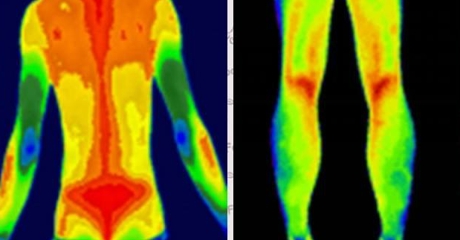

(插入示意圖:脊柱炎癥熱圖 – 紅色熱區(qū)與MRI病灶位置完全吻合)

血管病變預警

自動標注肢體溫差>1℃的區(qū)域(提示血栓風險)

動態(tài)監(jiān)測糖尿病足微循環(huán)變化

炎癥可視化

智能識別類風濕關(guān)節(jié)炎的“梭形熱區(qū)”

量化評估強直性脊柱炎進展程度